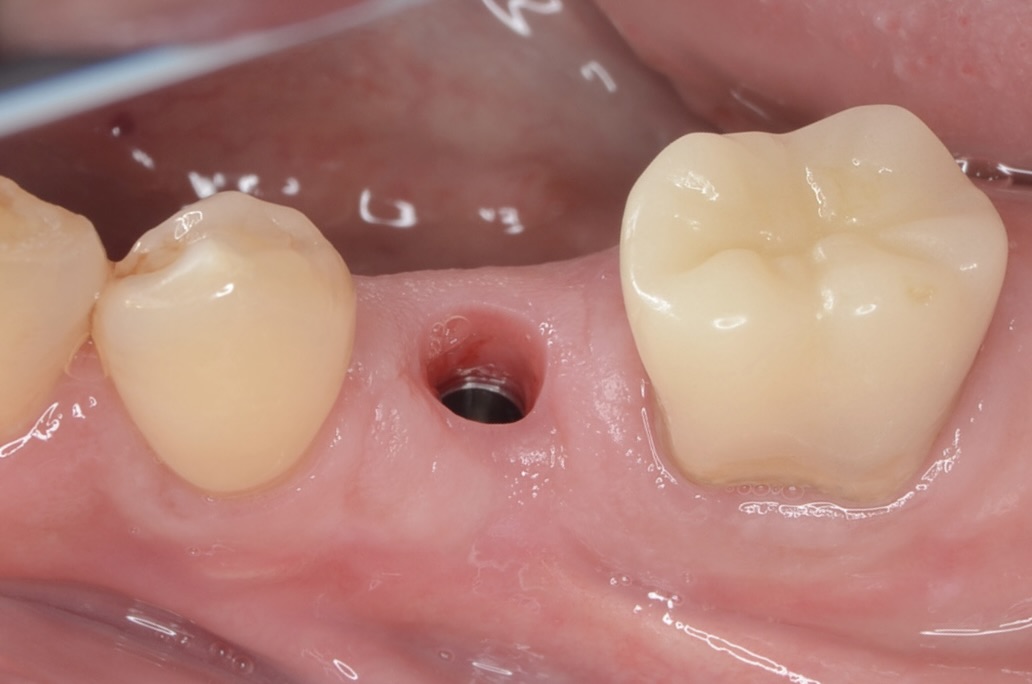

術後2ヶ月

ジンジバフォーマーを外したところです。綺麗な歯肉ができています。 -